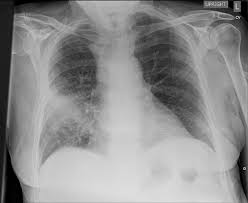

Cardiogenic Shock

Sit the patient up!

High flow O2

DIURESE!

Lasix no max dose (typically 40-120 mg IV )

Nitro patch or spray

Call for help if not improving